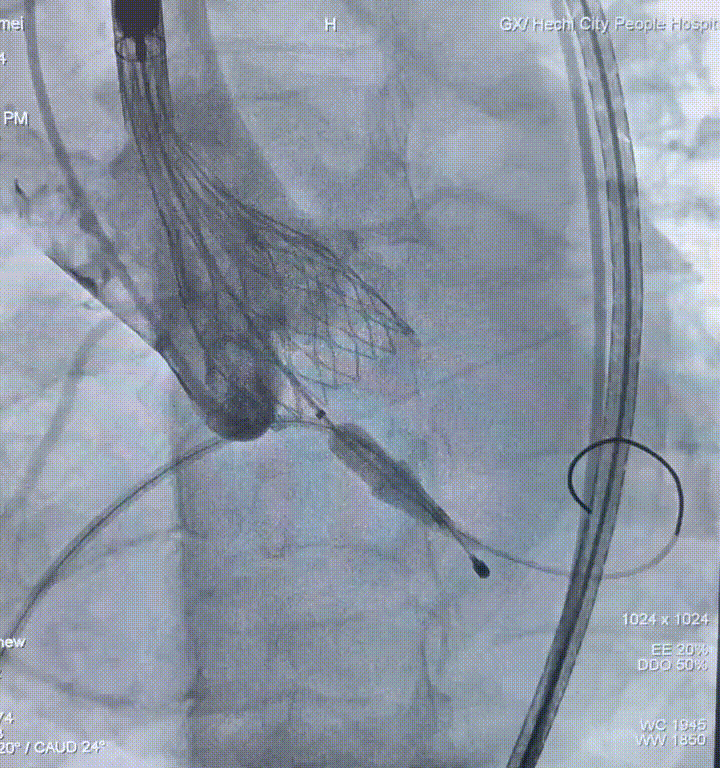

瓣膜释放

瓣膜释放至可回收极限位

释放完成